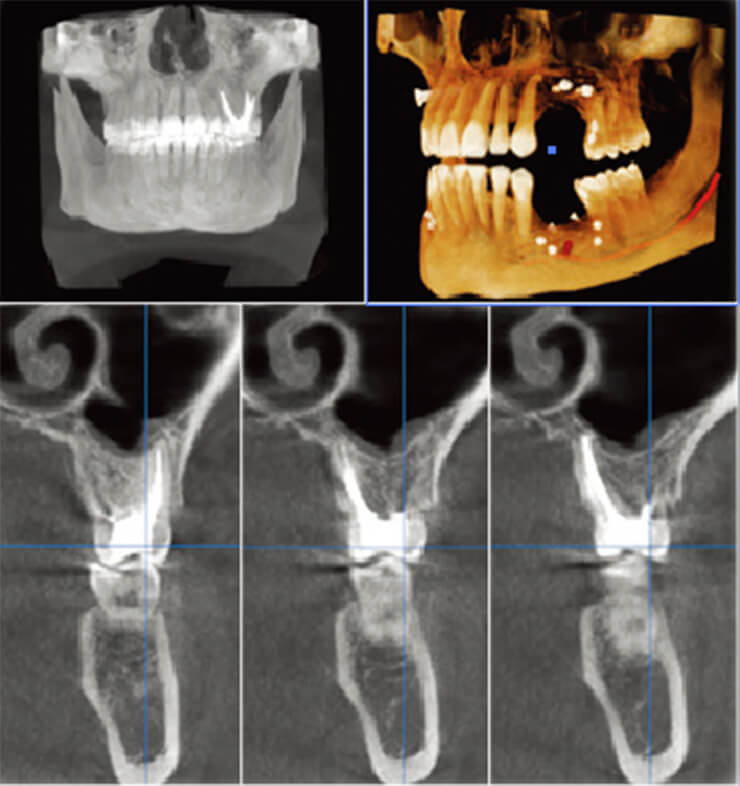

当院では精密治療に特化した顕微鏡治療ルームを設置しています。さらに最先端の3Dレントゲン(CT)、

治療用マイクロスコープを導入しています。これらの機器により高度な診断や精密な治療が可能です。